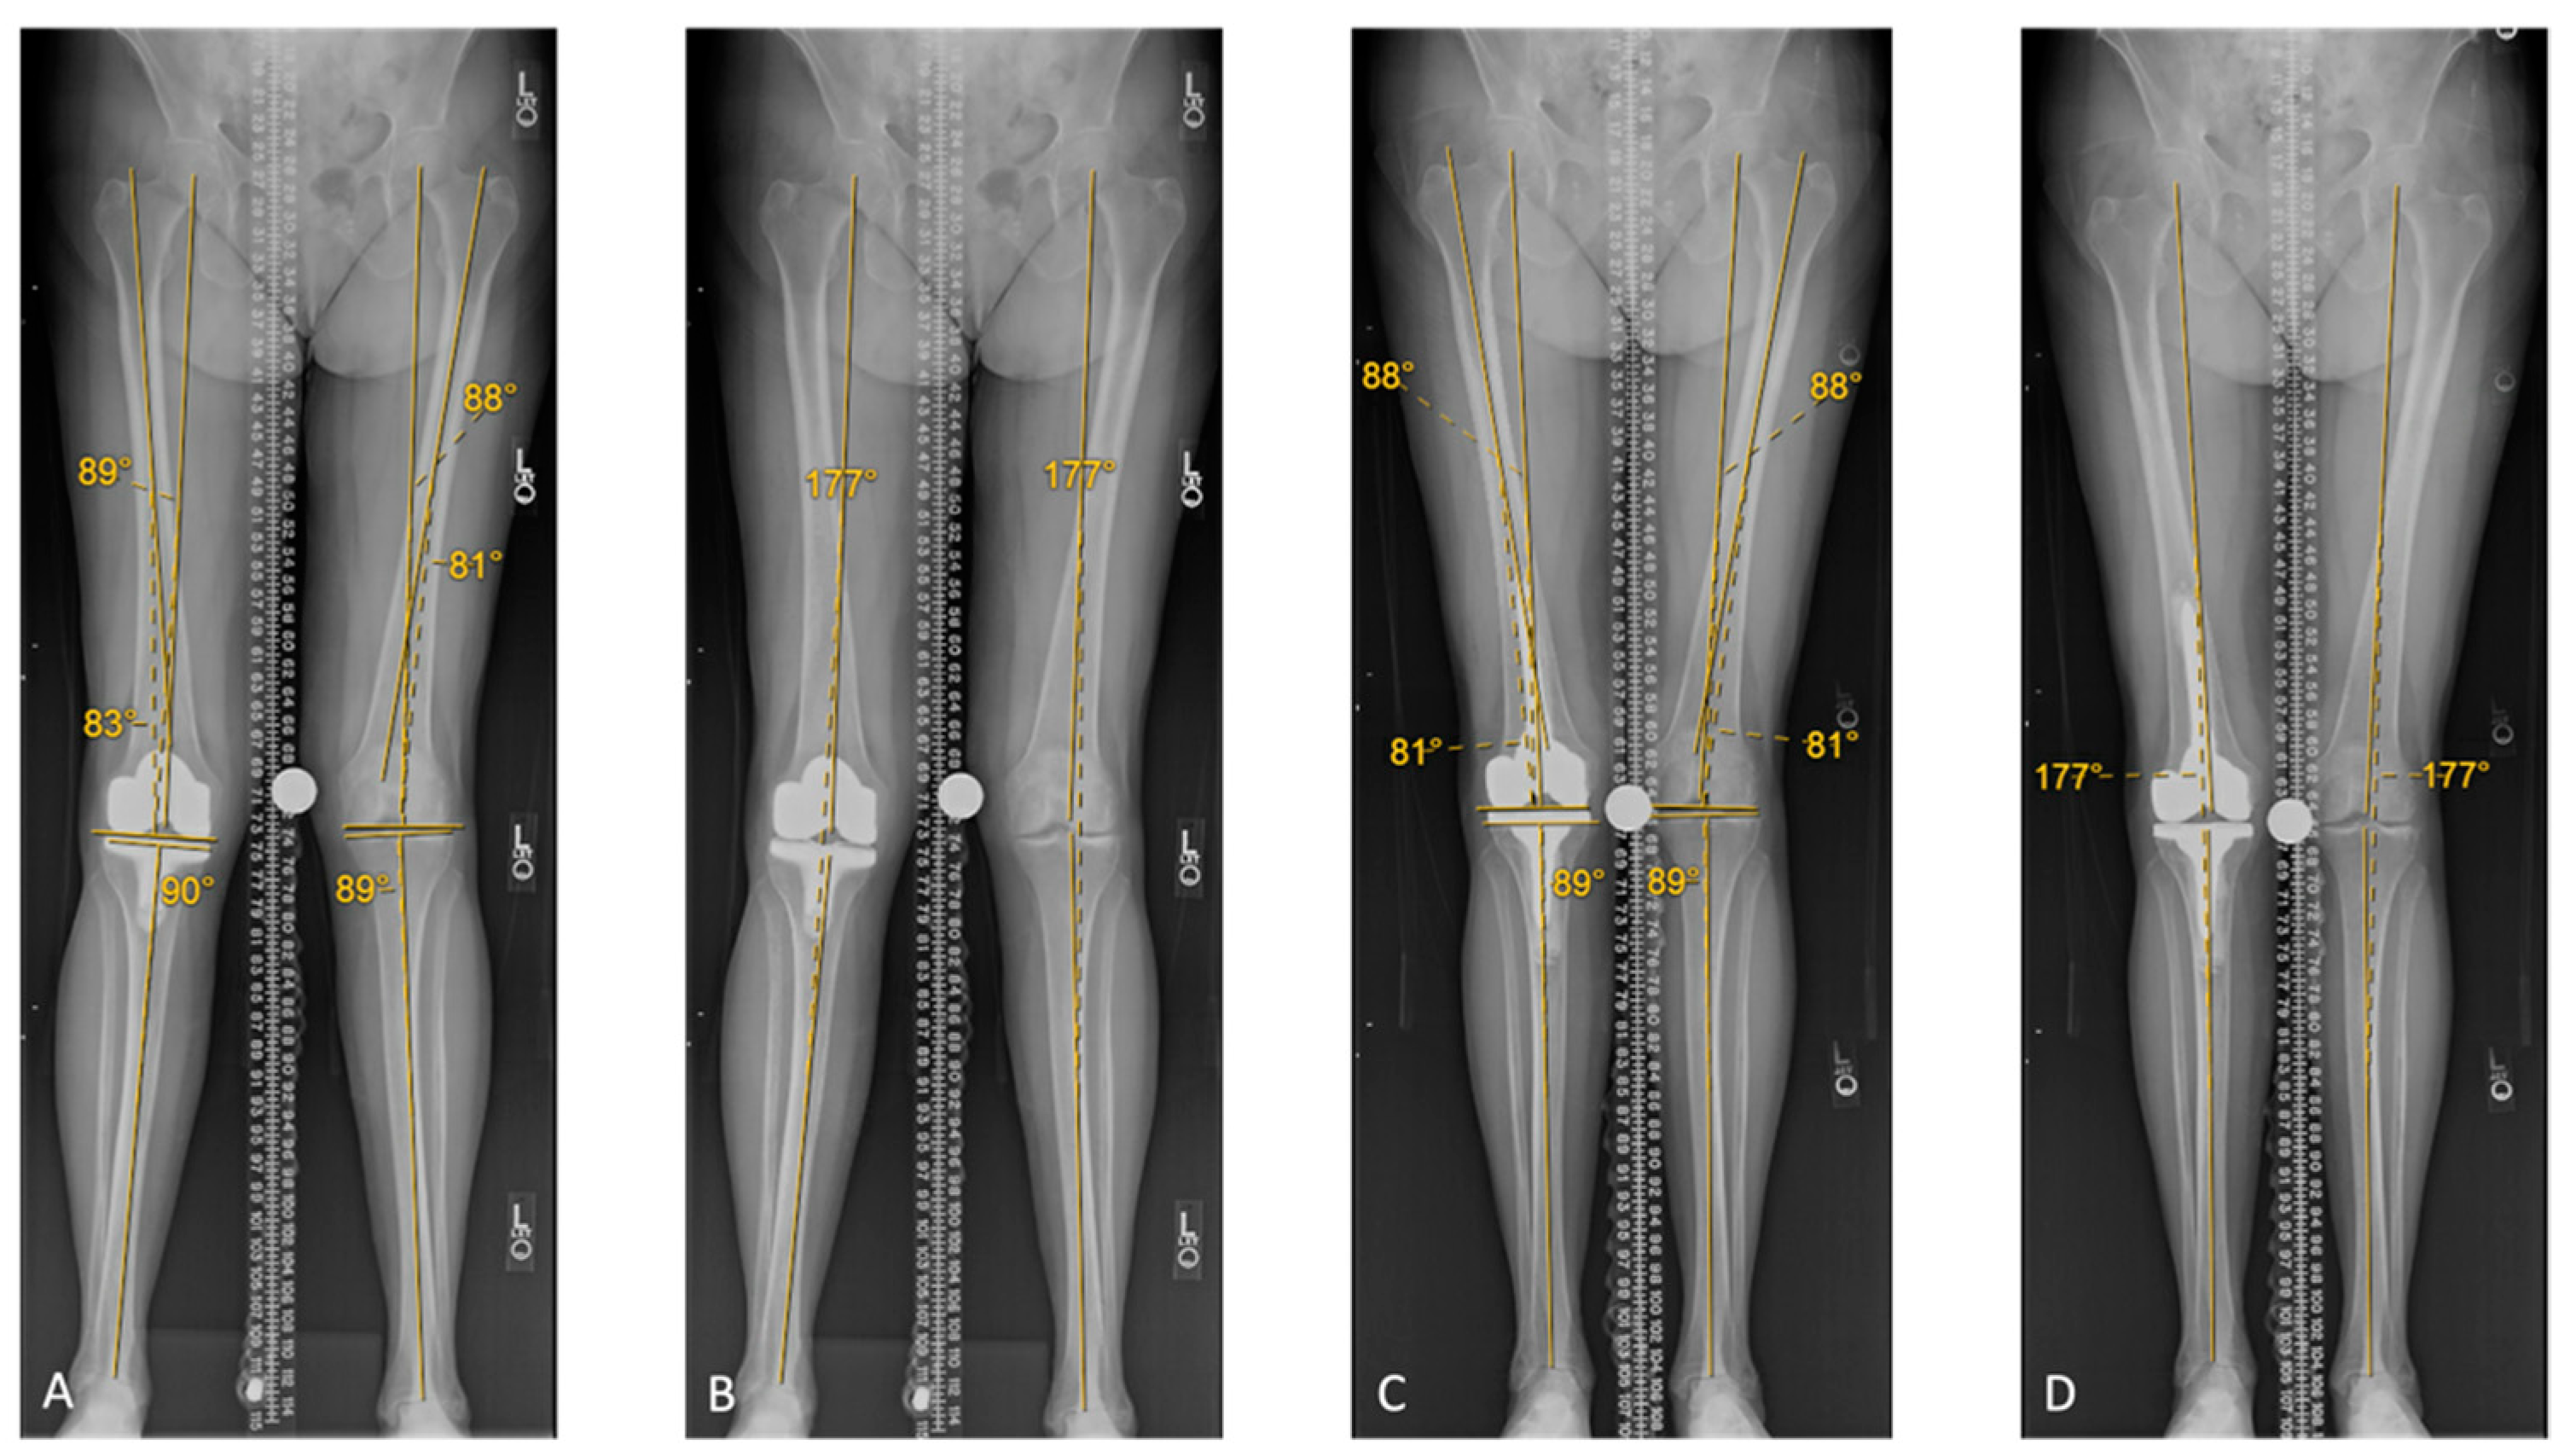

| Radiological Measurements | Native Alignment Means ± SD (Range) | Pre-Revision TKA Means ± SD (Range) | Post-Revision TKA Means ± SD (Range) | p-Value |

|---|---|---|---|---|

| Hip-Knee-Ankle Angle | 176 ± 5° (170 to 184°) | 181 ± 4° (177 to 183°) | 179 ± 2° (176 to 181°) | 0.005 * 0.051 ** |

| Mechanical Lateral Distal Femoral Angle | 88 ± 3° (83 to 91°) | 90 ± 2° (87 to 92°) | 88 ± 3° (83 to 91°) | 0.03 * 0.5 ** |

| Medial Proximal Tibial Angle | 88 ± 2° (85 to 90°) | 90 ± 1° (88 to 92°) | 88 ± 2° (85 to 90°) | 0.04 * 1 ** |

| Joint Line Obliquity Angle | 2 ± 3° (−2 to 5°) | −0.3 ± 3° (−5 to 4°) | 1 ± 3° (−2 to 5°) | 0.03 * 0.2 ** |

| Ground Talar Dome Angle | −1 ± 5° (−7 to 5°) | −7 ± 7° (−19 to −1°) | −2 ± 4° (−6 to 3°) | <0.001 * 0.3 ** |